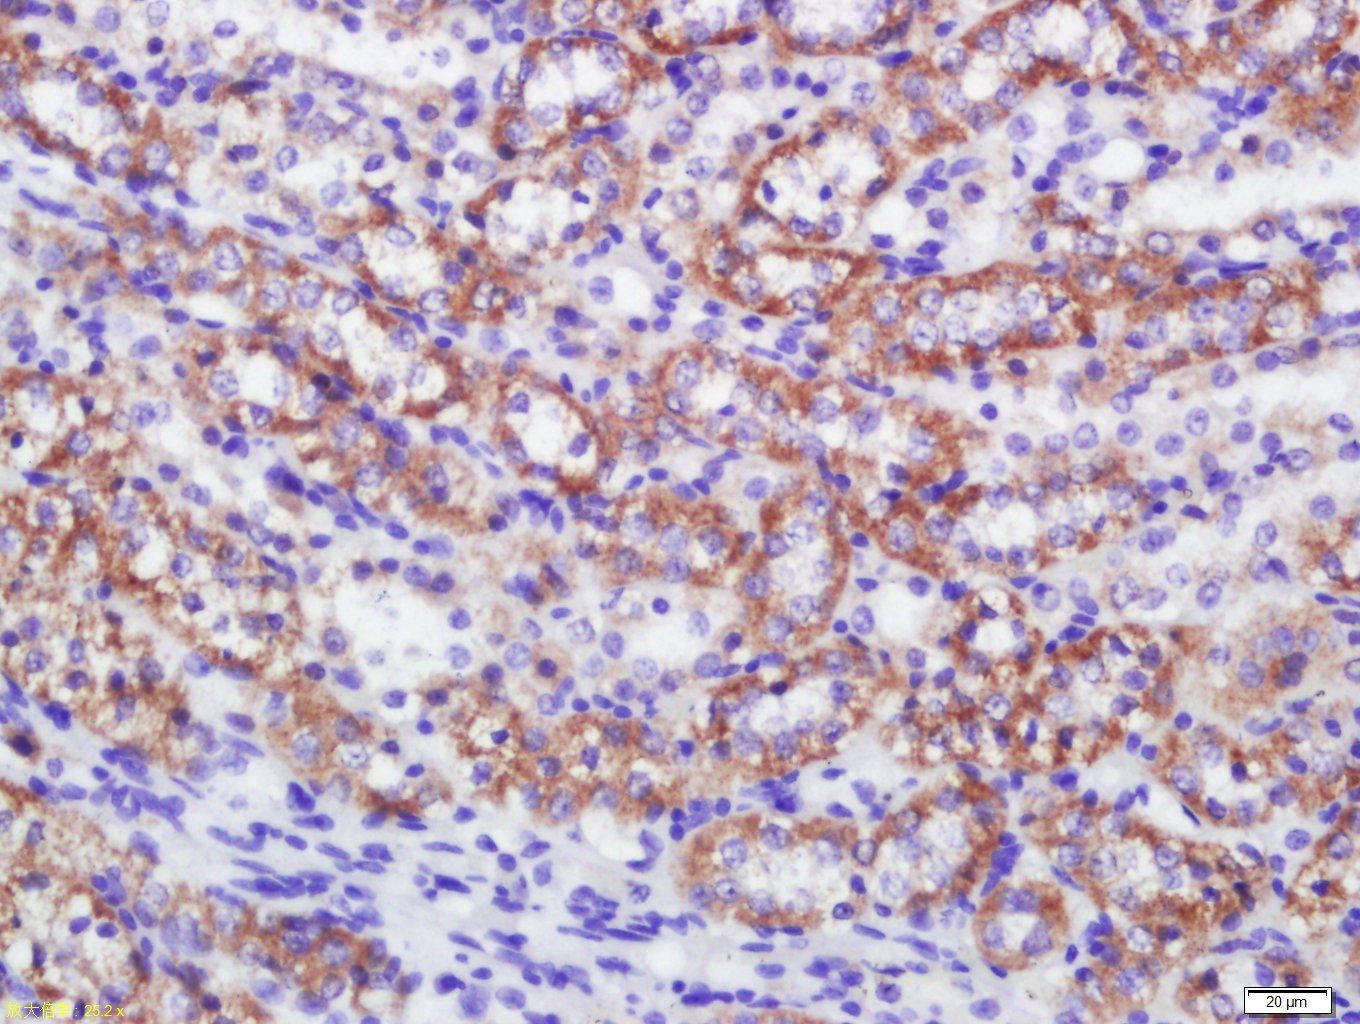

Paraformaldehyde-fixed, paraffin embedded (human kidney); Antigen retrieval by boiling in sodium citrate buffer (pH6.0) for 15min; Block endogenous peroxidase by 3% hydrogen peroxide for 20 minutes; Blocking buffer (normal goat serum) at 37°C for 30min; Antibody incubation with (C4orf52) Polyclonal Antibody, Unconjugated (bs-15196R) at 1:400 overnight at 4°C, followed by a conjugated secondary (sp-0023) for 20 minutes and DAB staining.